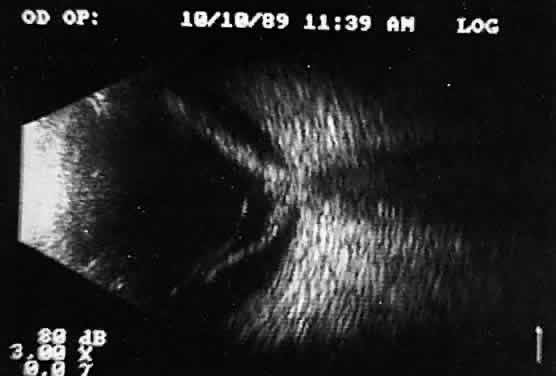

Ultrasound evaluation in patients with intraocular foreign bodies provides extremely useful additional information concerning associated ocular injuries and another method for localization, especially with nonmetallic intraocular foreign bodies not visible using x-ray techniques. Ultrasonically, foreign bodies have great reflectivity once the examining beam is placed perpendicular to a reflective surface of the foreign body. These abnormalities remain visible even with extreme attenuation of the examining signal (Fig. 16). Many metallic foreign bodies, especially those that are round or spherical, demonstrate “ringing,” a string of reflections that extend posterior to the foreign body in the form of a cometlike tail. Ringing is an ultrasound artifact produced by multiple “ping-pong” reflections of sound pulses within the foreign body before they return to the examining probe. The string of returning echoes produces an unusual display image.

Fig. 16. Contact B-scan and simultaneous A-scan: “buried” choroidal metallic foreign body. Note strong B-scan gray-scale image and high A-scan echo amplitude.